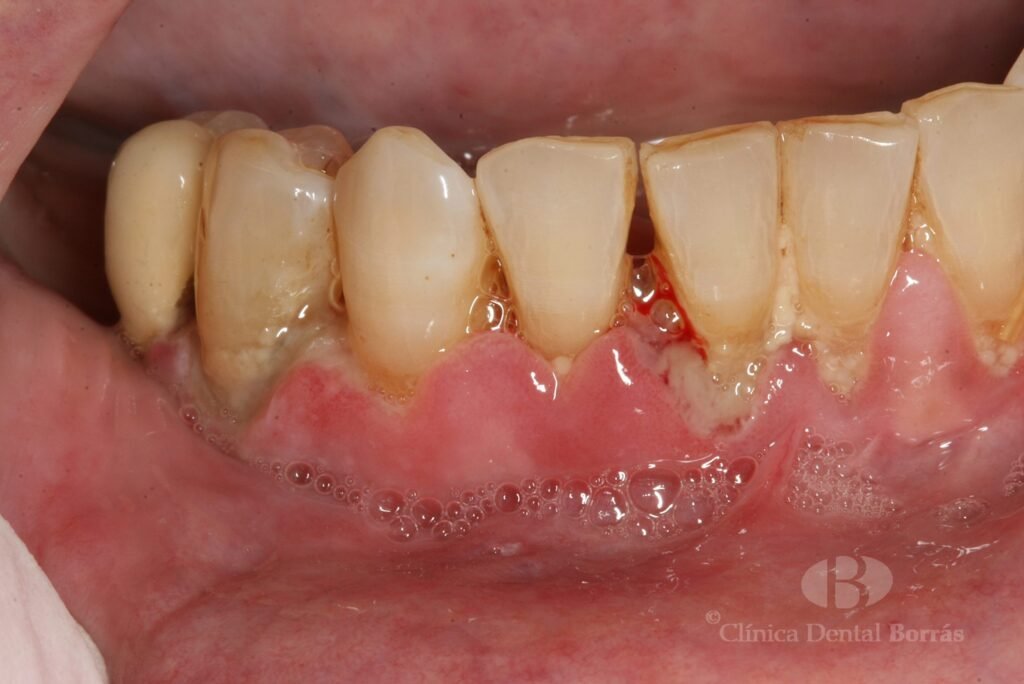

El gingivitis ulcerativa necrotizante (GUN) se refiere a una forma grave de gingivitis que afecta principalmente a las encías, causando dolor intenso y sangrado excesivo. Esta infección se caracteriza por la acumulación de bacterias dañinas en la boca, lo que puede llevar a úlceras en las encías y otros síntomas desagradables. A diferencia de la gingivitis leve, que solo afecta al tejido gingival, el gingivitis ulcerativa necrotizante (GUN) es una infección más profunda que puede afectar a múltiples áreas de la boca.

Los síntomas del gingivitis ulcerativa necrotizante (GUN) son generalmente dolorosos y afectan a múltiples áreas de la boca. Uno de los principales síntomas es el dolor intenso en las encías, que puede ser constante o intermitente. Además, se pueden observar sangrados excesivos en la boca, especialmente al cepillarse o al masticar. Las úlceras en las encías son otro síntoma común, que pueden causar incomodidad y dificultad para hablar o comer.

Además de los síntomas mencionados, algunos pacientes pueden experimentar inflamación de las encías, lo que puede hacer que las encías se hinchen y se tornen rojas. En casos más graves, la infección puede extenderse a otras partes del cuerpo, como el cuello o la mandíbula, lo que puede llevar a complicaciones adicionales. Es importante destacar que estos síntomas pueden variar en severidad de un paciente a otro, y algunos pueden experimentar solo algunos de ellos.